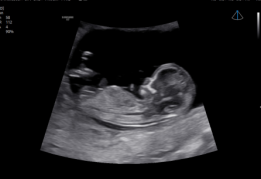

V7 OB

V7 OB – Ecógrafos para Obstetricia y Ginecología

El V7 OB optimiza la atención de la salud femenina, desde fertilidad hasta seguimiento del embarazo. Combina Crystal Architecture™ con Intelligent Assist™, permitiendo flujo de trabajo eficiente, imágenes de alta calidad y diagnósticos confiables.

HDVI™ mejora la visualización de bordes y detalles finos en imágenes volumétricas, lo que facilita la identificación de estructuras anatómicas complejas del feto y órganos femeninos. Esta tecnología avanzada asegura imágenes más claras y detalladas, apoyando diagnósticos obstétricos y ginecológicos de alta precisión.

RealisticVue™

RealisticVue™ proporciona un renderizado 3D con detalle anatómico realista y percepción de profundidad, permitiendo visualizar rostros fetales y estructuras críticas con claridad. Esta función es ideal para seguimiento de desarrollo fetal y estudios de anatomía detallada, ofreciendo a los especialistas herramientas confiables para la evaluación prenatal.